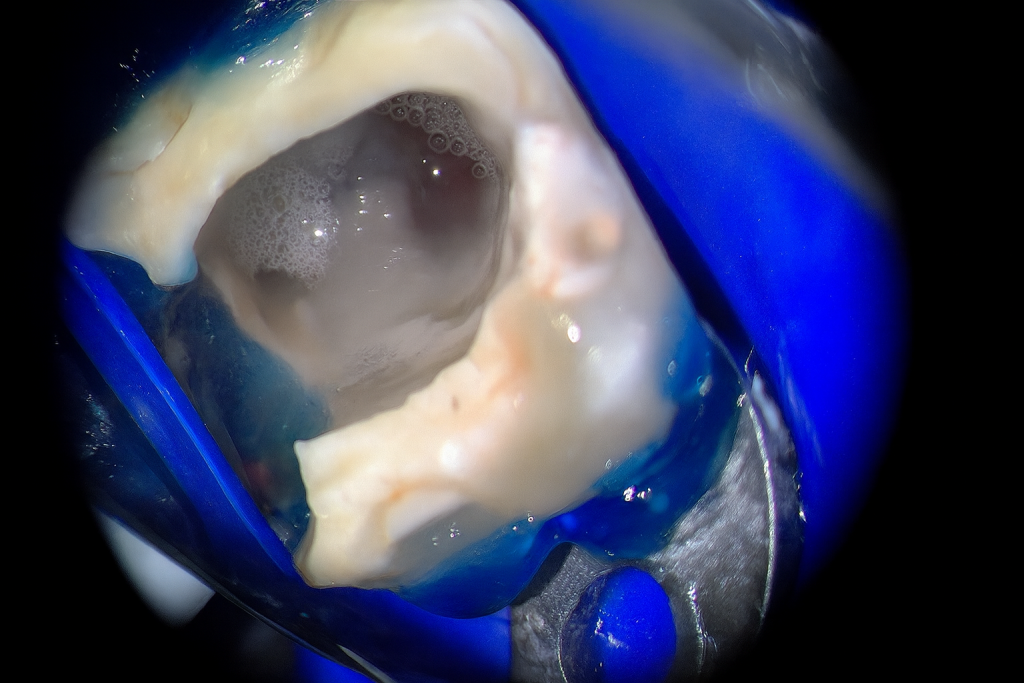

Rubber-dam isolation achieved. Conservative access refined under a dental microscope (Fig 2). The broken instrument was visualized in the coronal third of the distal canal. Ultrasonic tips (ET18D and ProUltra Endo) were used to trephine dentin around the fragment and safely dislodge it.

- Fig 2: Microscopic access and visualization of fractured instrument.